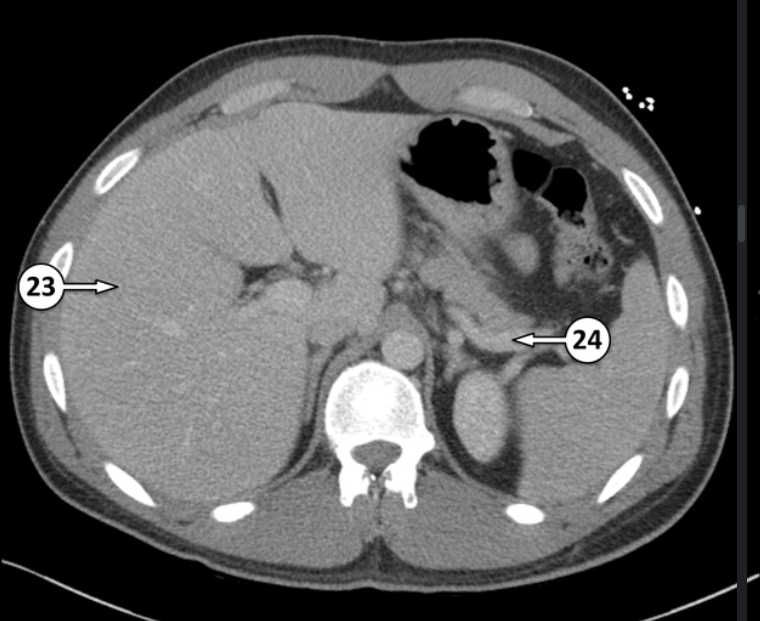

Label 23 and 24

Segment V of the liver

Splenic vein